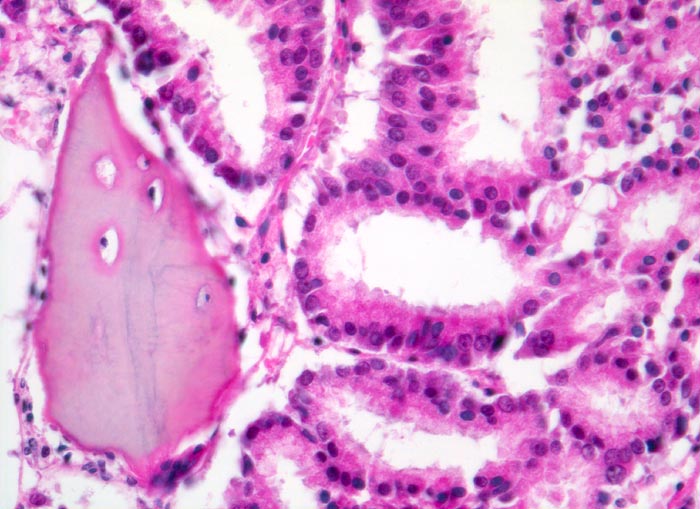

Morphologische Merkmale:

• Fehlen von blutbildendem Knochenmark.

• Infiltration des Knochemarks durch kleine dichtgepackte, kribriforme Strukturen ausbildende Karzinomdrüsen.

• Osteplastische Metastase: Faserknochenneubildung zwischen vorbestehenden Trabekeln.

• Anhand der Histologie kann lediglich die Diagnose einer Metastase eines Adenokarzinoms gestellt werden. Kleine, solide Verbände bildende Tumordrüsen und grosse Nukleolen sind typisch für ein Prostatakarzinom. Die Diagnose muss aber durch den Vergleich mit der Morphologie des Primärtumors oder eine Immunhistochemische Untersuchung (PSA, PSAP) bestätigt werden.